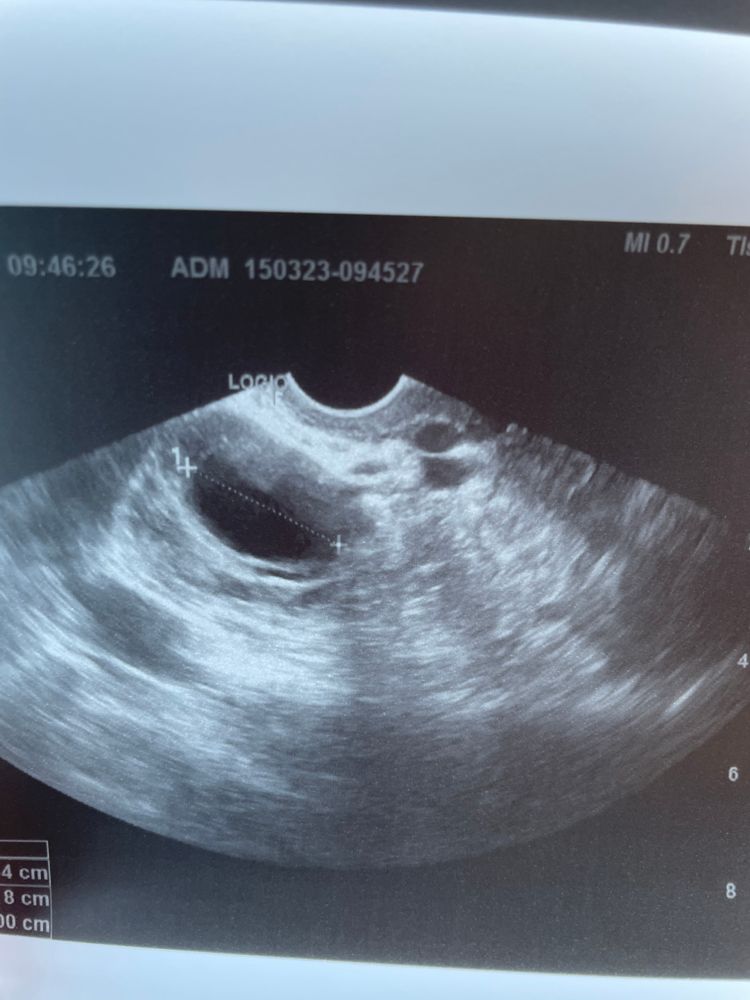

Фолликул или ЖТ?

На узи жидкость , но врач так и не сказала что это, фолликул так вырос или киста желтого тела?!

Фолликул в понедельник был 18 мм. Был ПА, после чего заболел живот (возможно овуляция, обычно ее чувствую ) .А сегодня, в среду уже что-то размером 26 мм.

фото прикрепляю

но у вас больше похоже на ЖТ, фоллик с ровными четкими краями, а ЖТ с краями как будто желток чуть сварили, как раз очень похоже на ваше узи